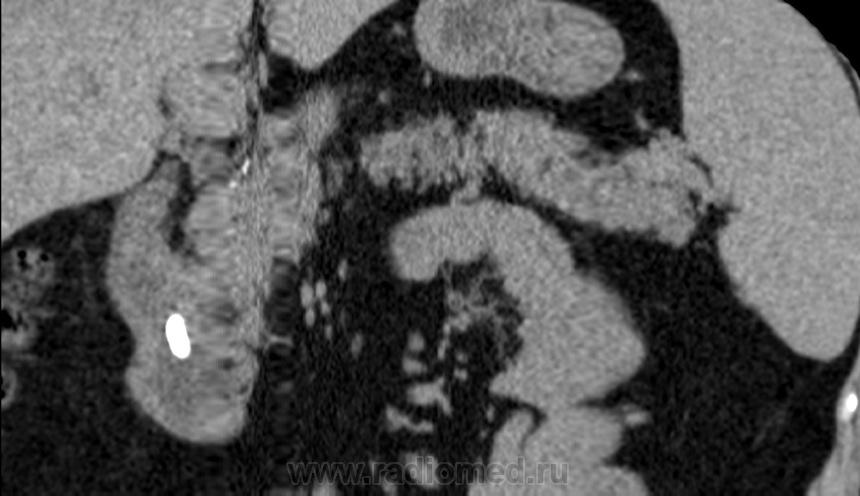

Итак пациент мужчина 34 года, в анамнезе - 16 эпизодов острого панкреатита (!). Пациенту была выполнена ЭРХПГ которая выявила наличие двух стриктур протока Вирсунга в области головки поджелудочной железы (доброкачественная стриктура Вирсунгова протока). На представленных мной изображениях определяется неоднородная структура поджелудочной железы с гиподенсными участками в области тела/хвоста и наличием паренхиматозных кальцификатов (b & c). Такая картина указывает на хронический панкреатит. В области головки визуализируется стент (a), установленный в Вирсунгов проток, с свободным концом в просвете 12-ти перстной кишки. Такое стояние стента является правильным. На данный момент, единственной адекватной терапией при доброкачественных стриктурах протока поджелудочной железы (и при некоторых опухолях исходящим из протока или обтурирующих его, когда невозможно выполнить резекцию) является эндоскопическое стентирование протока, что обеспечивает нормальный отток секрета поджелудочной в кишечник.

Верно. Об обструкции стента можно заподозрить только при наличии расширения протока дистальнее, или если пациент поступит с новым приступом острого панкреатита. В профилактических целях, стент периодически меняют.